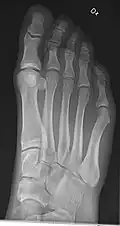

- Foot / Toes - Dorsoplantar, Oblique and Lateral.[19]

-

Normal right foot by dorsoplantar projection -

Oblique projection -

Lateral projection